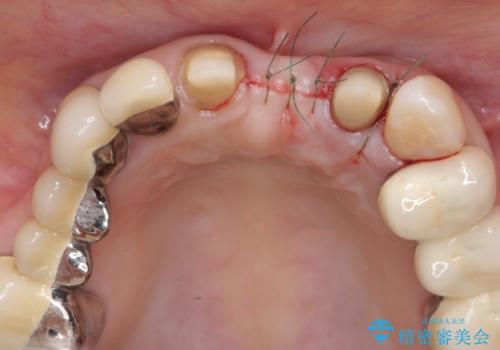

- 前歯の審美障害、見た目の改善を希望され来院されました。

歯肉縁下カリエスも認められるため、挺出を行いセラミックブリッジを審美的に新製します。

- 47万円(仮歯×3・ファイバーコア×2・ジルコニアクラウン×3 歯の挺出)費用は治療当時の料金となります